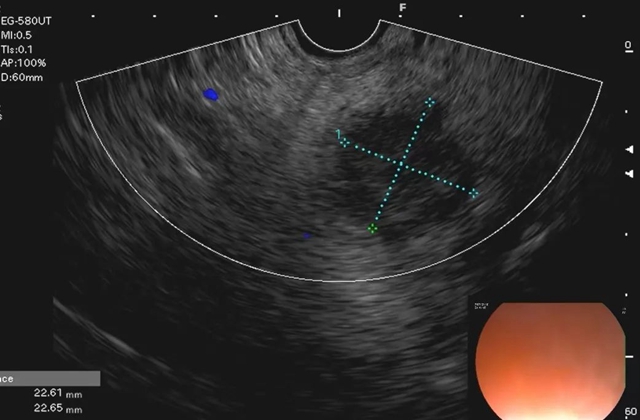

经过超声内镜全面扫查,最终在税先生的胰腺头颈部发现了一个2.2×2.3cm大小的低回声病灶,超声下显示比之前CT检查时更大。

在多普勒超声引导下,谨慎避开周围血管,选择合适的穿刺位置后,李丽副教授用穿刺针对病灶进行了反复多次抽吸。穿刺过程十分顺利,成功获取了有效的病灶组织。